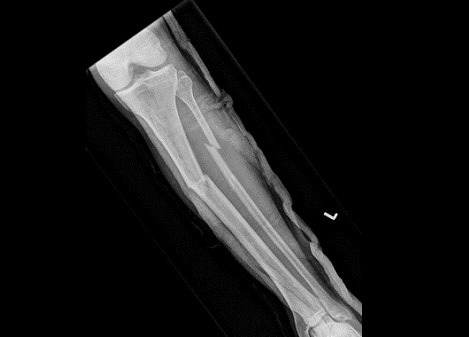

Fig6. - Midshaft tibia fracture.

Fig6. - Treated with an intramedullary nail